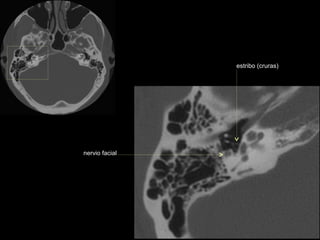

seno timpánico

receso del n. facial

nervio facial (3era)

estribo (cruras)

nervio facial

ventana oval